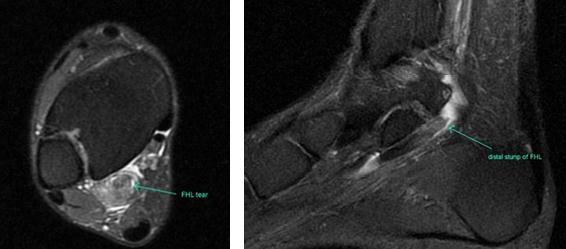

Прежде всего, это боль по задне-внутренней поверхности голеностопного сустава. Возможно «защёлкивание» большого пальца при его сгибании. Хруст, крепитация по задне-внутренней поверхности голеностопного сустава при активных движениях. При физикальном осмотре определяется боль при сгибании большого пальца через сопротивление, при форсированном подошвенном сгибании в голеностопном суставе, при этом боль отсутствует в области первого плюсне-фалангового сустава. Для диагностики повреждения сухожилия длинного сгибателя большого пальца стопы целесообразно выполнение МРТ, при этом обнаруживается скопление жидкости вокруг сухожилия на уровне голеностопного сустава, изменение сигнала от самого сухожилия.

При разрывах сухожилия длинного сгибателя большого пальца помимо остро возникшей боли и отёка по задне-внутренней поверхности голеностопного сустава определяется выраженная слабость подошвенного сгибания большого пальца стопы.